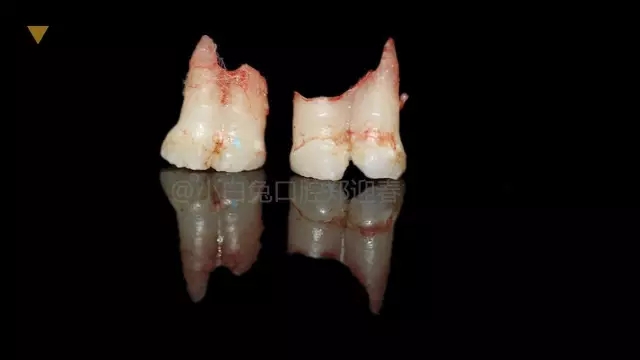

拔出后的離體牙